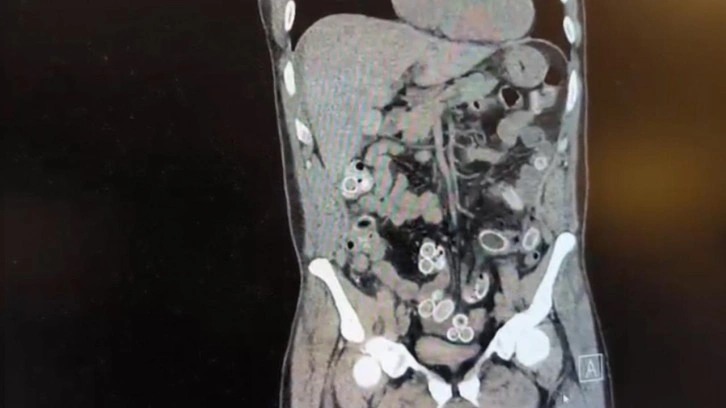

Fas’tan yaklaşık 3 bin kilometre uzaklıktan uçakla Türkiye’ye gelen Cüneyt G., 2 gün sonra karın ağrısı şikayetiyle Fulya’daki özel bir hastaneye başvurdu. Yapılan muayenenin ardından Cüneyt G.’nin tomografisi çekildi. Şüphelinin mide ve bağırsaklarında yabancı madde tespit edilmesi üzerine hastane yetkilileri durumu polis ekiplerine bildirdi.

İhbar üzerine çalışma başlatan Beşiktaş Asayiş Büro Amirliği ekipleri, doktorlarla görüşme gerçekleştirdi. Doktorların değerlendirmesi sonrası ameliyata alınan Cüneyt Ç.’nin bağırsaklarından, toplam ağırlığı 259,7 gram olduğu öğrenilen 49 esrar macunu çıkarıldı. Şüpheliye ait 1 adet cep telefonu da hastane yetkilileri tarafından polis ekiplerine teslim edildi.